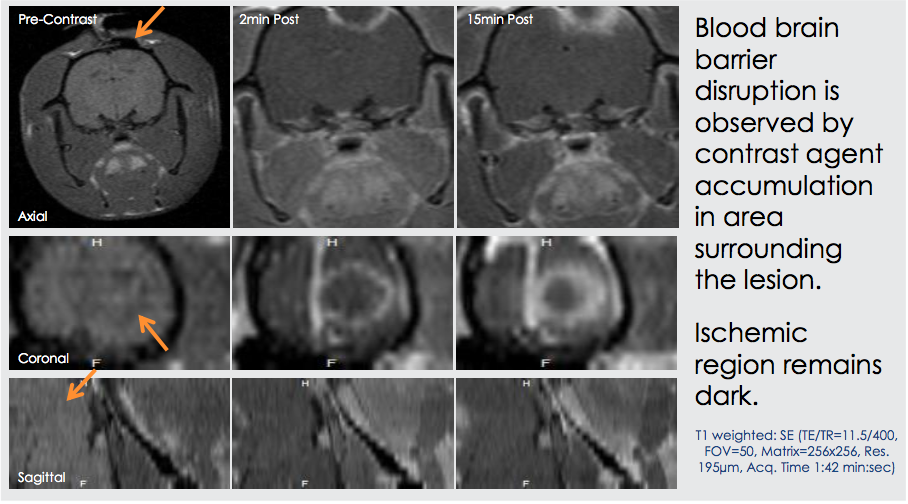

Glioblastoma Tumor contrast Enhanced MRI

Blioblastoma Tumor Dynamic Contrast Enhanced MRI